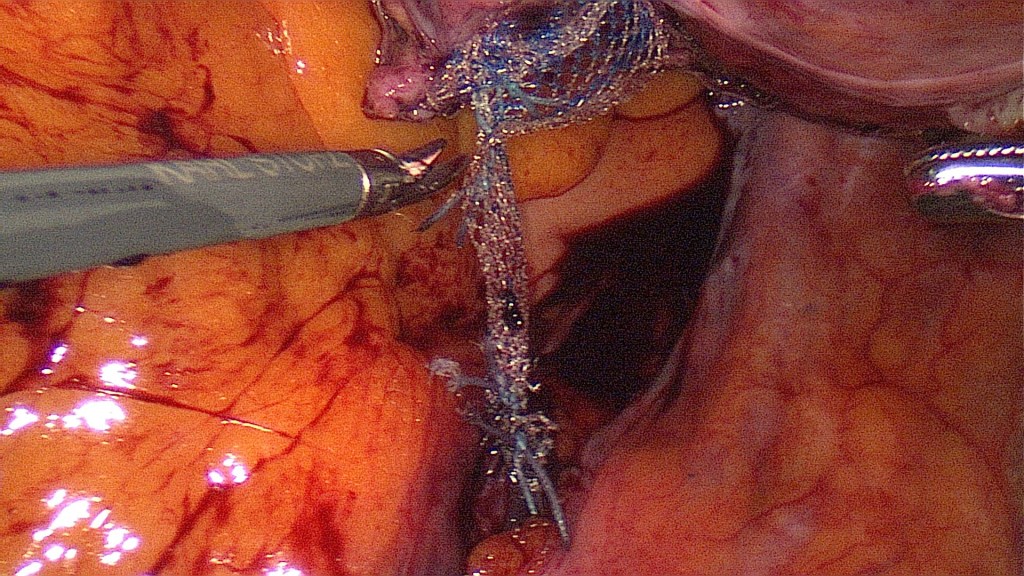

Fixation of mesh on the cervix.

The mesh has been fixed on the sacral promontory and now only needs to be brought retroperitoneally.